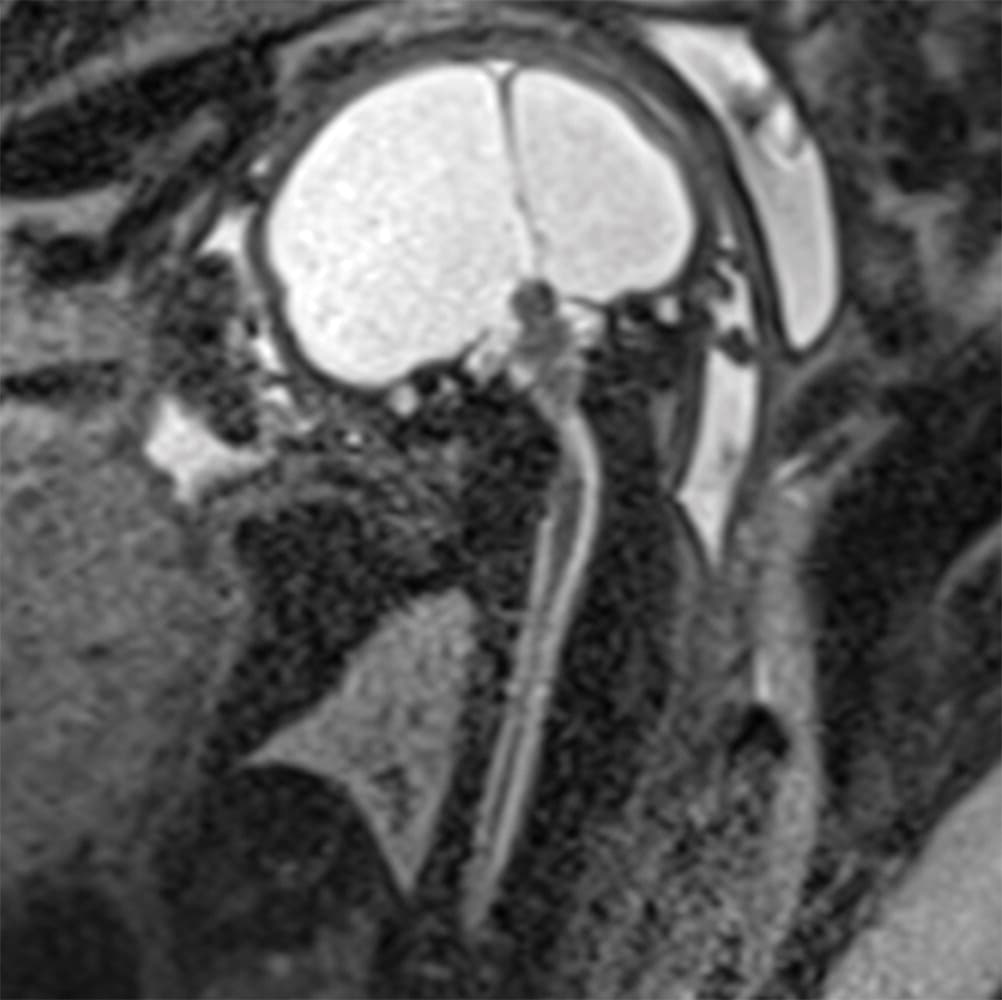

Investigadores brasileños difundieron este martes el mayor número hasta ahora disponible de imágenes computarizadas, resonancias magnéticas y ultrasonidos, de bebés y fetos infectados con el virus del Zika. El daño es mucho mayor del que anticipaban.

Así describe la radióloga brasileña Fernanda Tovar-Moll lo que vio al analizar centenares de imágenes computarizadas, resonancias magnéticas y ultrasonidos de 45 bebés que se contagiaron de zika en el vientre materno en el estado de Paraíba, en el noreste del país, donde el brote ha sido severo.

La mayoría nació con microcefalia, cuya característica más llamativa es que tienen el cerebro y la cabeza más pequeña. Pero muchos sufren una escala y severidad de daño mucho peor en partes importantes del cerebro como el cuerpo calloso, que conecta los dos hemisferios; el cerebelo, que juega un papel significativo en el movimiento, equilibrio y habla; y los ganglios basales, que controlan el pensamiento y la emoción.

Tovar-Moll es coautora de un estudio publicado el martes en la revista Radiology y fue liderado por la doctora Patricia Soares de Oliveira-Szejnfeld, a quien se le da crédito por establecer el vínculo entre el zika y la microcefalia en Brasil.